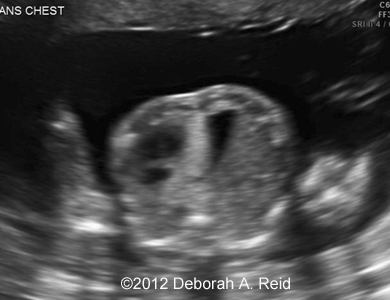

Ultrasound showed left-sided congenital diaphragmatic hernia with mild polyhydramnios.

The left-sided congenital diaphragmatic hernia contained a large portion of the bowel, spleen, stomach and the tip of the left lobe of the liver. In addition to the congenital diaphragmatic hernia, a sub-diaphragmatic sequestration was also noted which was confirmed by MRI.

Figure 1-10: The left-sided congenital diaphragmatic hernia contained a large portion of the bowel, spleen, stomach and the tip of the left lobe of the liver